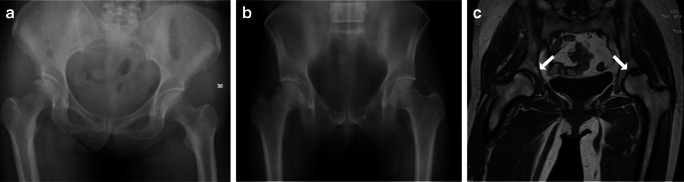

Fig. 3.

a DR shows no apparent abnormality. b DTS shows (c) CT/MR diagnosis of osteonecrosis of the femoral head